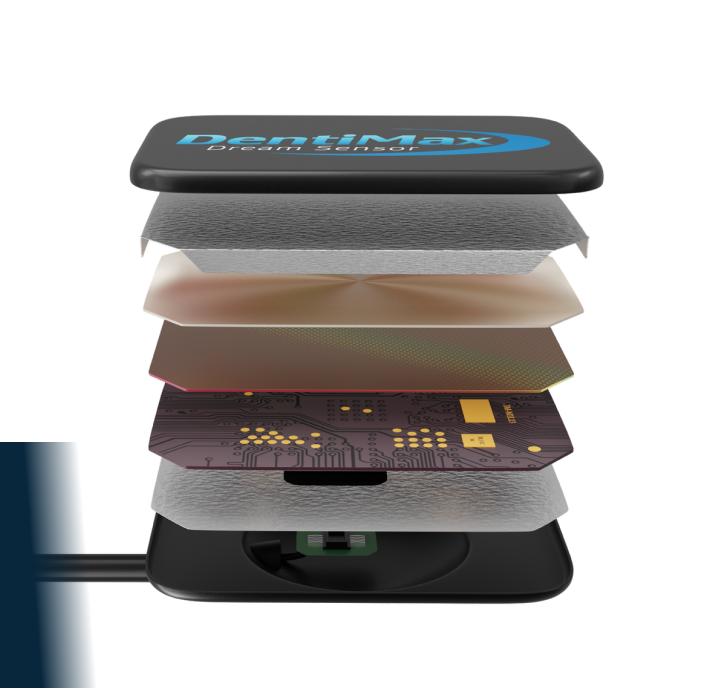

Dental Sensors Built For Comfort

& Durability

Our sensors are designed to make the DentiMax Dream Sensor one of the thinnest sensors on the market today. It’s easy to position and its beveled edges maximize comfort to ensure a painless experience for patients.

- Direct USB port connection

- Round corners for patient comfort

- Kevlar® reinforced cable

- Thinnest CMOS on the market (5.3mm)

- Waterproof sealed housing